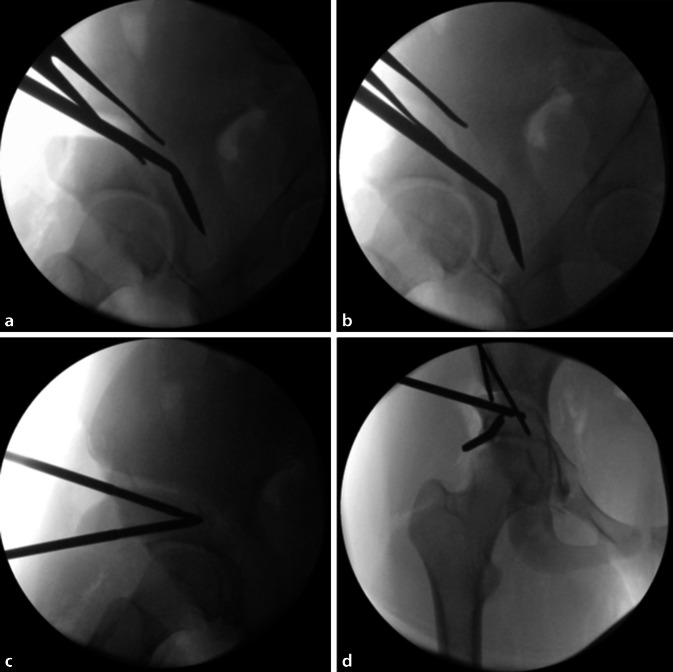

(Abb. 3, 4, 5, 6, 7, 8, 9, 10, 11, 12, 13, 14, 15, 16 und 17).

Gefahr von intraazetabulären Frakturen: Die intraoperative Durchleuchtung ist obligat, um Komplikationen bei der Durchführung einer PAO zu vermeiden. Insbesondere hat sich die Durchleuchtung als zuverlässiges diagnostisches Werkzeug zur Vermeidung von Verletzungen der hinteren Säule und intraartikulärer Osteotomien erwiesen.